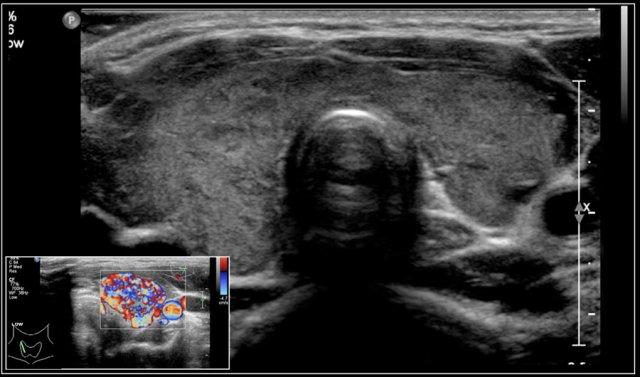

Đây là hình ảnh của một bé gái 16 tuổi mắc cường giáp.

Tuyến giáp to lan tỏa với tình trạng sung huyết.

Chẩn đoán cuối cùng là bệnh Graves.

Bệnh nhân được điều trị bằng I-131.

Trong bệnh Graves, tuyến giáp cũng to ra và cho thấy sự tăng tưới máu.

Trên siêu âm Doppler màu, hình ảnh này được mô tả như một địa ngục lửa với màu đỏ và xanh.